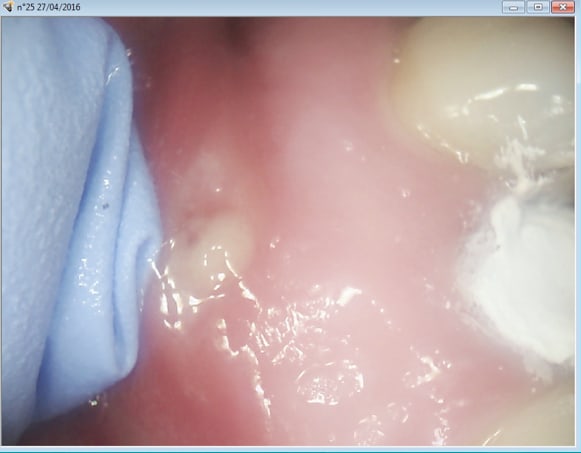

Merde il y avait une fistule . je m'en suis aperçu juste après la remise du devis pour l'ic coiffe. Ca ne se voit pas trop à la radio ? Je peux y aller sans risque d'indu ? Parce que voyez vous ca me fait chier d'avoir travaillé pour rien. -)

Capture d e cran 2016 04 27 19.08 - Eugenol

8tercecn7hisbbqbde2nil4nyxrw - Eugenol